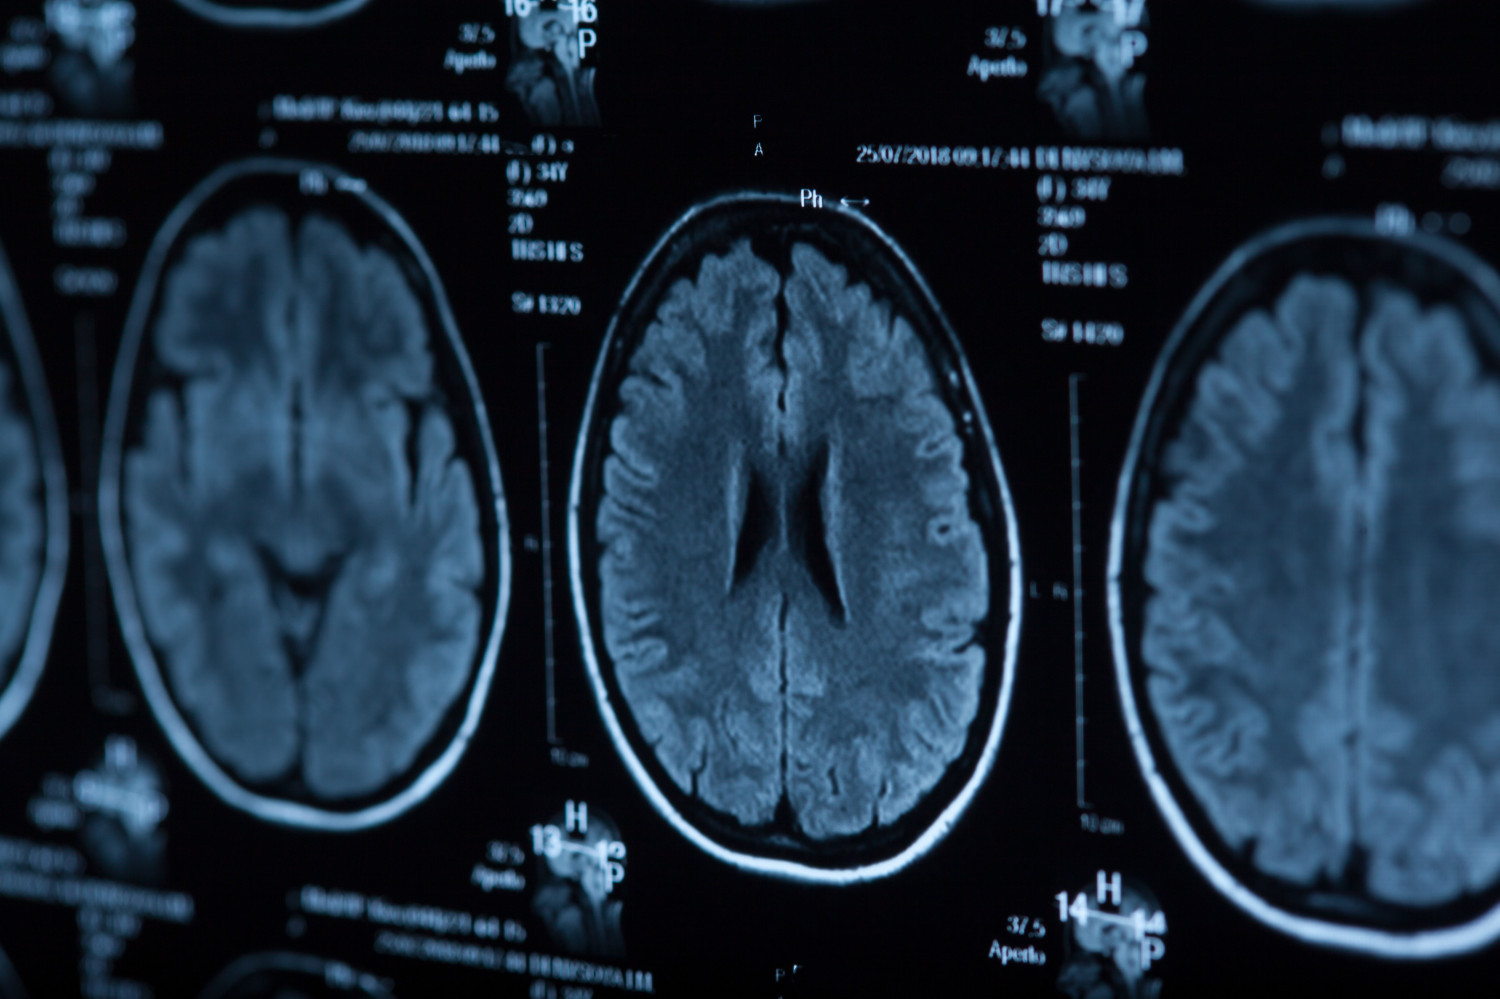

| В исследовании приняли участие 3154 пациента с нетяжелым некардиоэмболическим ишемическим инсультом или транзиторной ишемической атакой высокой степени риска. Половина участников получала пероральный колхицин по 0,5 мг в день в сочетании с обычной терапией, остальные – только стандартную терапию. Длительность наблюдения составила 36 месяцев. Оценивали частоту развития комбинированного неблагоприятного исхода, включавшего первый фатальный или повторный нефатальный ишемический инсульт, инфаркт миокарда, остановку сердца или госпитализацию по поводу нестабильной стенокардии. |